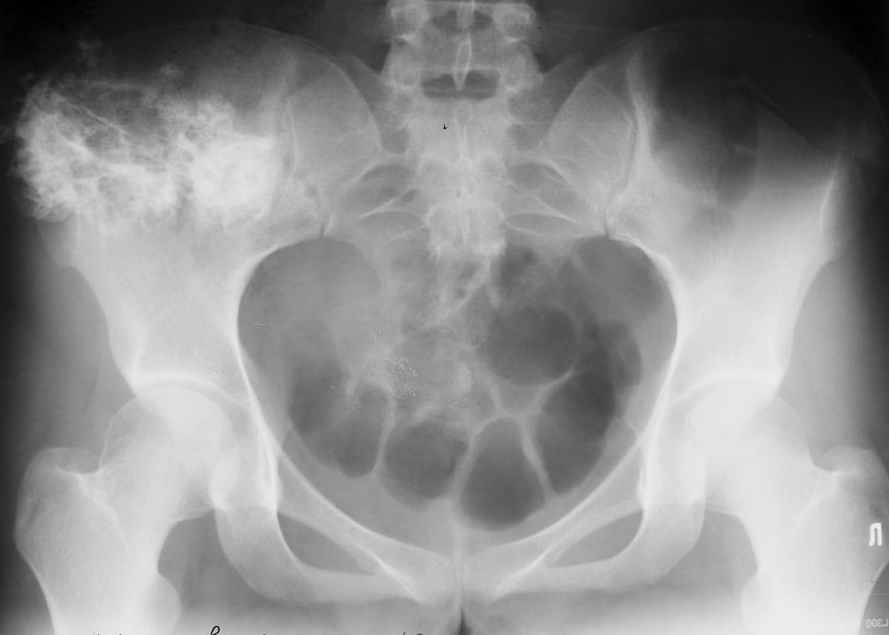

Уважаемые коллеги! К нам поступила пациентка 16 лет с диагнозом: остеохондрома крыла правой подвздошной кости.

Учитывая большие размеры образования, необходимо удаление его с резекцией крыла подздошной кости вместе с ее гребнем. Предполагается наличие большого дефекта. Поделитесь опытом закрытия таких дефектов.

Судя по КТ, проблема не в гребне а в крыле...

Опухоль имеет задне-наружное нправление...

При этом гребень можно и не трогать, а вот большую дырку в крыле сделать будет наверное необходимо...